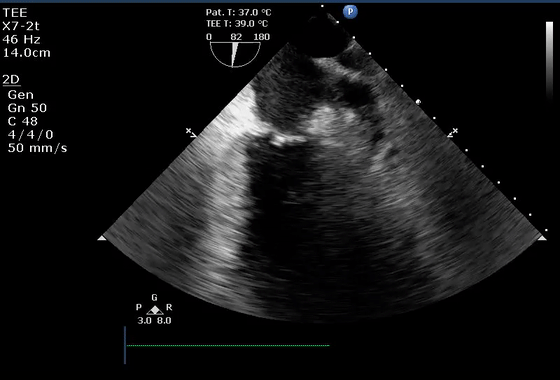

10、经食管超声图像伪像

虽然上面介绍的主要集中在常规经胸超声心动图,但上述伪像也经常在经食管超声心动图中遇到。图10显示了经食管超声心动图中一些常见的伪像。在这方面最相关的临床情况是(1)排除LAA中的血栓(图10E和10F)和(2)排除主动脉夹层(图10G和10H)。

图10经食管图像伪影。

(A)二尖瓣小叶的混响伪影,距离探头正好两倍,表现为左心室腔内的导线(视频15)。

(B)机械主动脉瓣在右心室(RV)(星号)的大部分上投射声学阴影,并在侧面(箭头)投射混响(彗星尾)(视频16)。

(C)房间隔穿刺的导管,由于在(中空)导管上下侧的反射,出现一系列紧密间隔的混响(箭头),并且由于在探头本身的反射,在距离探头两倍的距离处出现一个混响。

(D)疑似两个平行的主动脉(Ao)的镜像伪影(星号)。注意血流也产生镜像伪像(视频17)。

(E)左心耳疑似血栓的混响伪影。从多个角度(见图F)进行分析证实存在华法林嵴的混响(星号),而不是真正的血栓(视频18-19)。

(G)在升主动脉(视频20)中延伸的钙化窦管连接(箭头)的旁瓣伪影(箭头)不应被误解为夹层。

(H)同样,升主动脉中的回声可能会被误解为夹层。